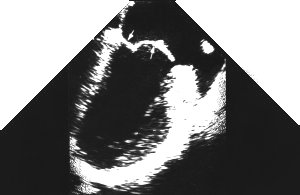

5. ME Long axis - 'ME LAX'

6. The following view is sub-optimal, as the view of the ventricle is somewhat oblique, and the aortic valve isn't well seen.